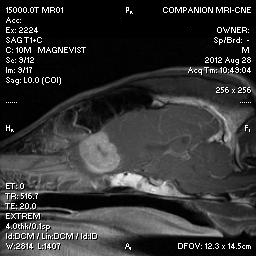

Companion MRI is the only full-time small-animal veterinary magnetic resonance imaging center in central Connecticut serving clients from all over New England, New York, and New Jersey. MRI for dogs and cats has the same clinical indications and diagnostic benefits as MRI scans for humans. We are excited to offer this affordable, superior diagnostic tool to all veterinarians and clients.